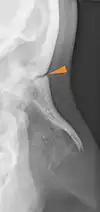

The frontonasal suture (Latin: Sutura frontonasalis) is a cranial suture that is found in the human skull, connecting the frontal bone and the two nasal bones.[1] This suture meets the internasal suture at the nasion. It is crucial in the study of cranial development and forensic analysis.